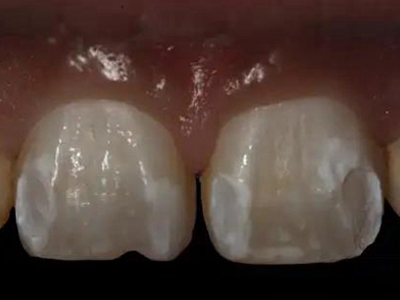

酸蚀症牙齿有白斑图

酸蚀症患者的牙齿可出现白斑,形状不规则,境界较清,大部分位于靠近牙根处,其中一颗门牙白斑基础上还有较大的褐色斑块,部分患牙已出现凹陷的牙齿缺损,需进行充填修复治疗。

酸蚀症牙齿缺损表面凹凸不平图

酸蚀症可使牙齿表面出现缺损,两颗上门牙表面有局部凹陷,使牙面凹凸不平,质地硬且无明显颜色改变,该病可能是盐酸腐蚀牙齿导致。